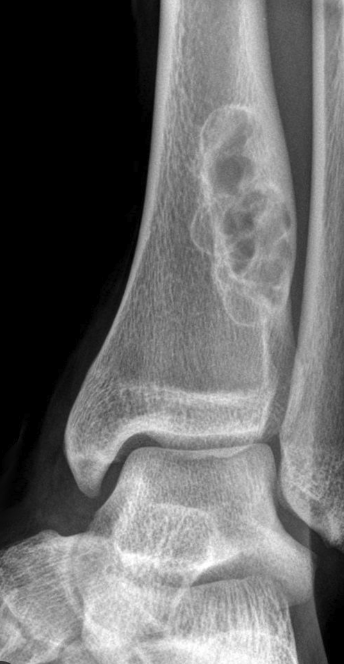

Giant Cell Tumor (GCT) Key Criteria - Physis MUST be closed - Non Sclerotic Border - Abuts the articular surface

26

Giant Cell Tumor (GCT)

20-30 = physis closed (MUST) Location: Knee - Most common Association: ABC (can turn into them) Quasi malignant (5% - lung mets) Fluid levels on MRI